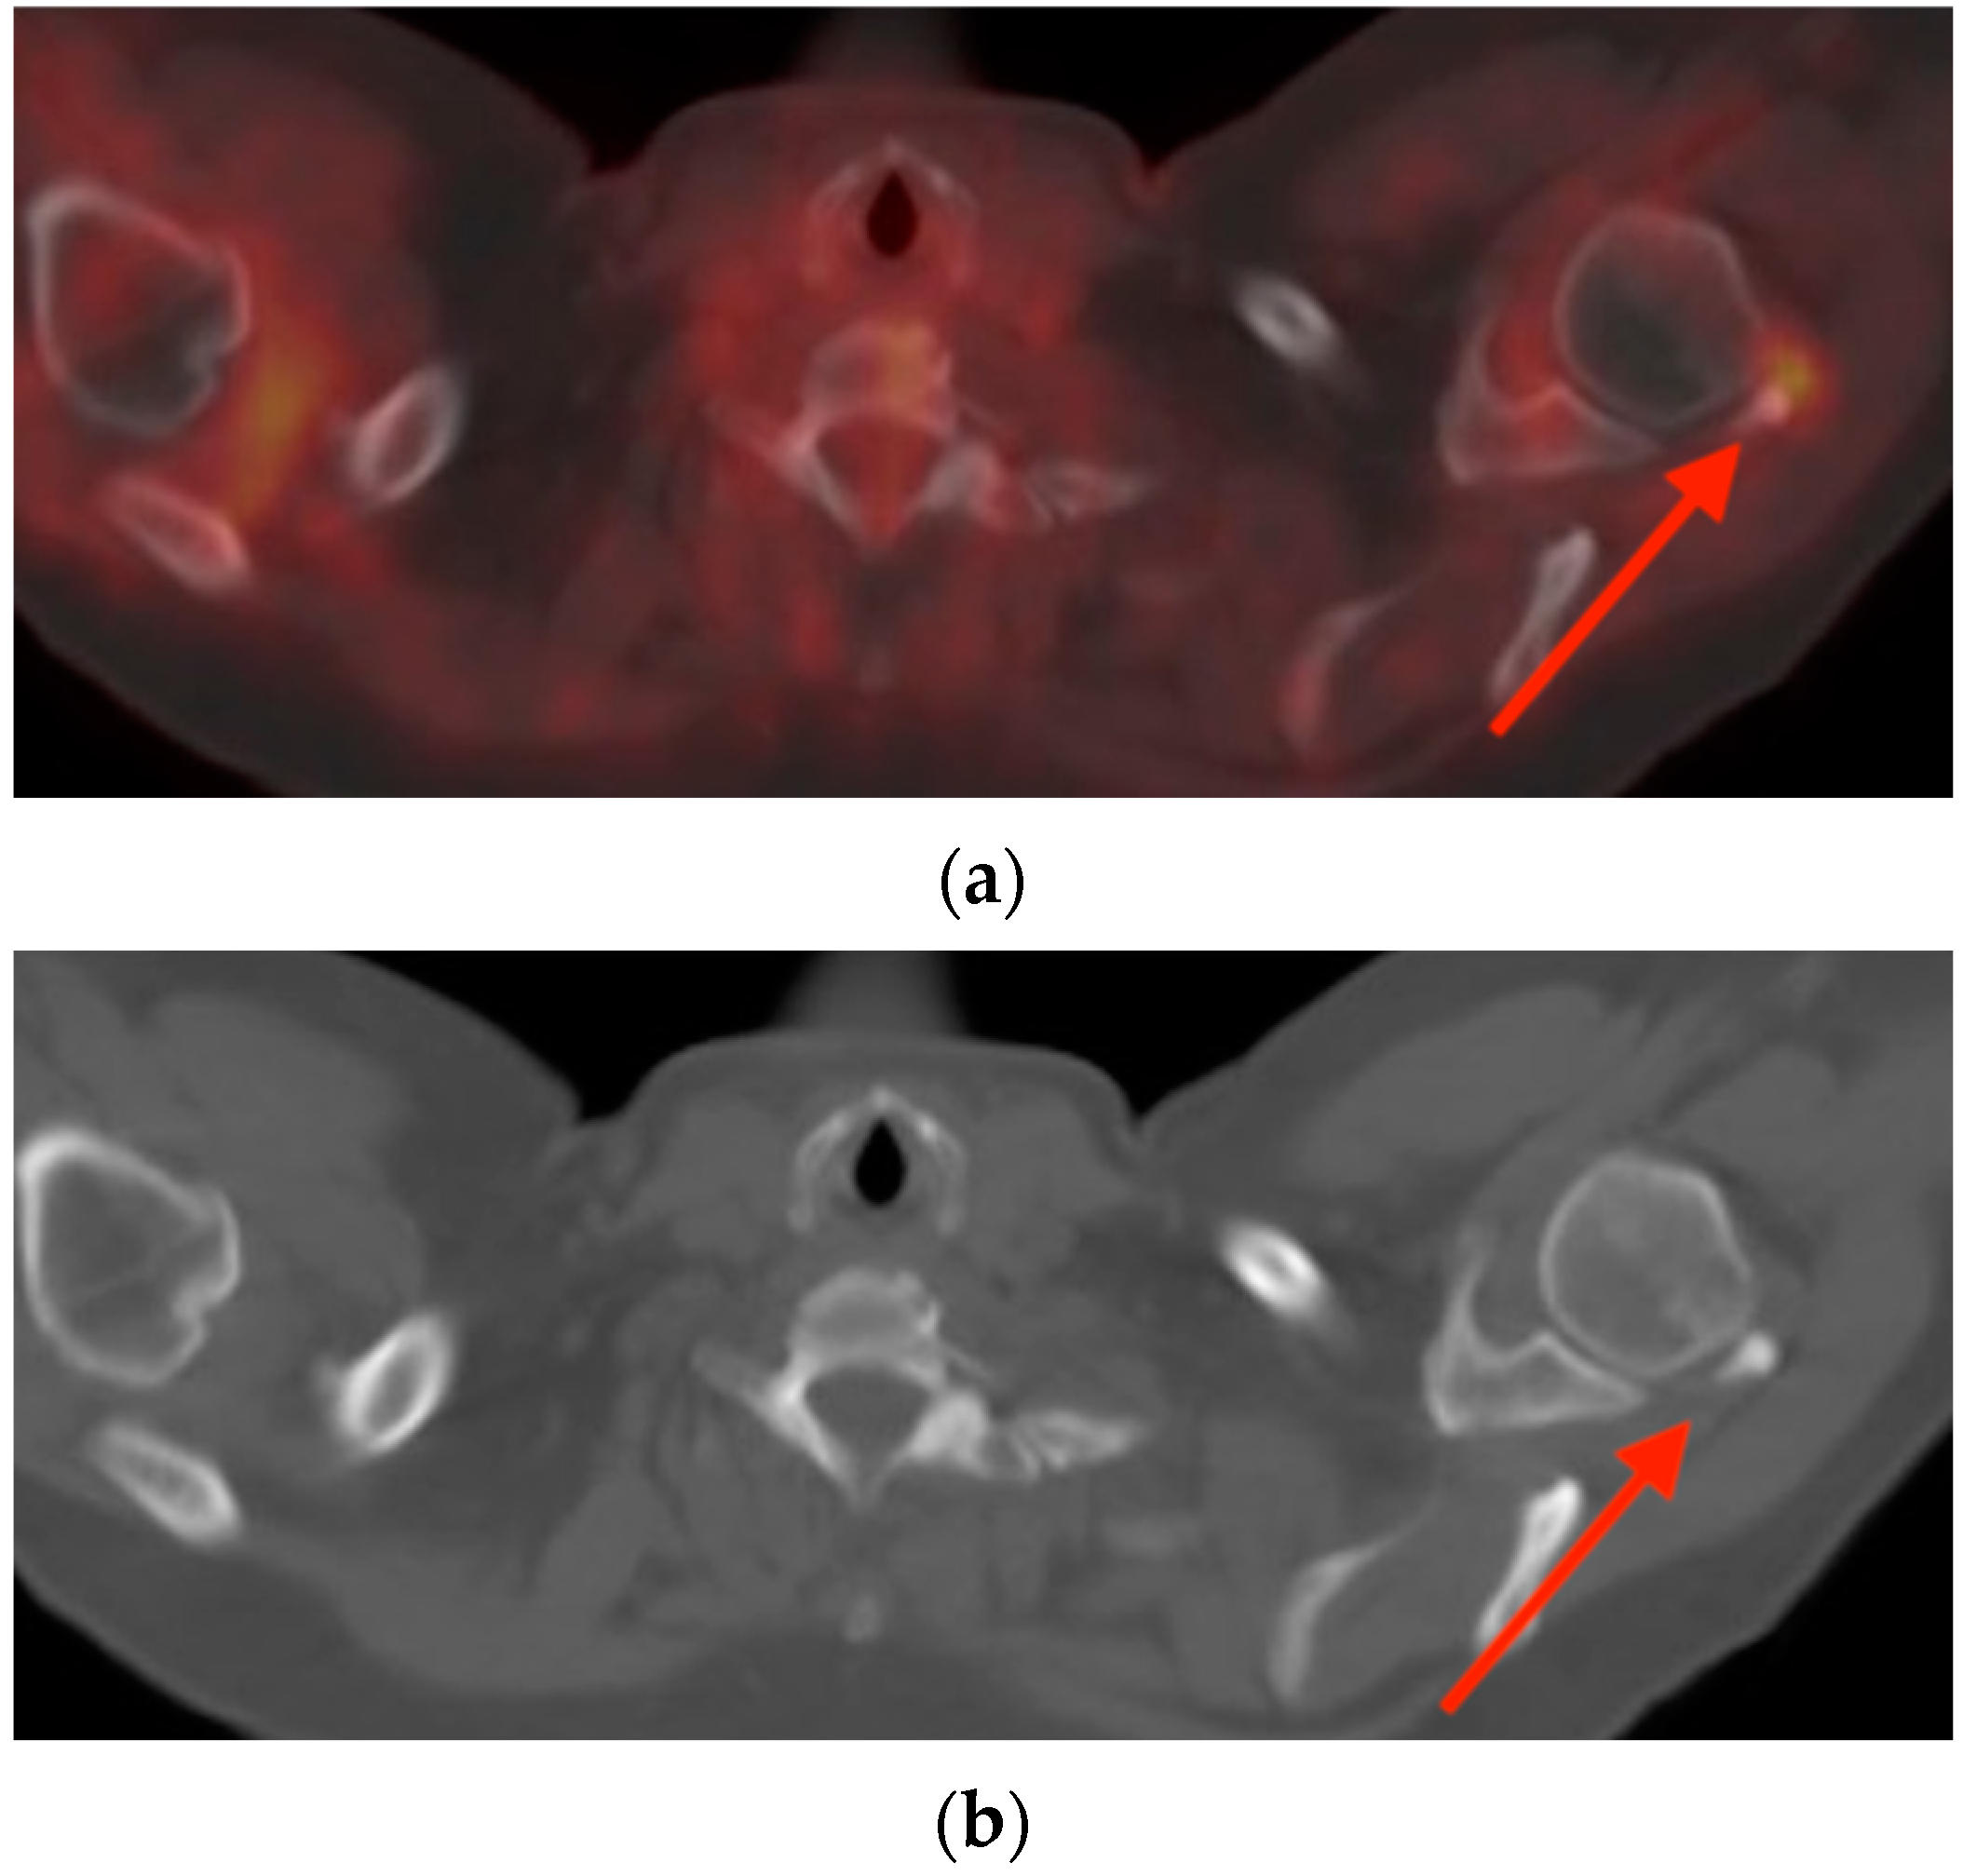

3.3. Calcific Tendinopathy

- Loew, M.; Jurgowski, W.; Mau, H.C.; Thomsen, M. Treatment of calcifying tendinitis of rotator cuff by extracorporeal shock waves: A preliminary report. J. Shoulder Elbow Surg. 1995, 4, 101–106. [Google Scholar] [CrossRef]

- Almedghio, S.; Garneti, N. The Acute and Chronic Presentation of Gluteus Medius Calcific Tendinitis—A Case Report of Two. J. Orthop. Case Rep. 2014, 4, 48–50. [Google Scholar] [CrossRef]

- Flemming, D.J.; Murphey, M.D.; Shekitka, K.M.; Temple, H.T.; Jelinek, J.J.; Kransdorf, M.J. Osseous involvement in calcific tendinitis: A retrospective review of 50 cases. AJR Am. J. Roentgenol. 2003, 181, 965–972. [Google Scholar] [CrossRef]